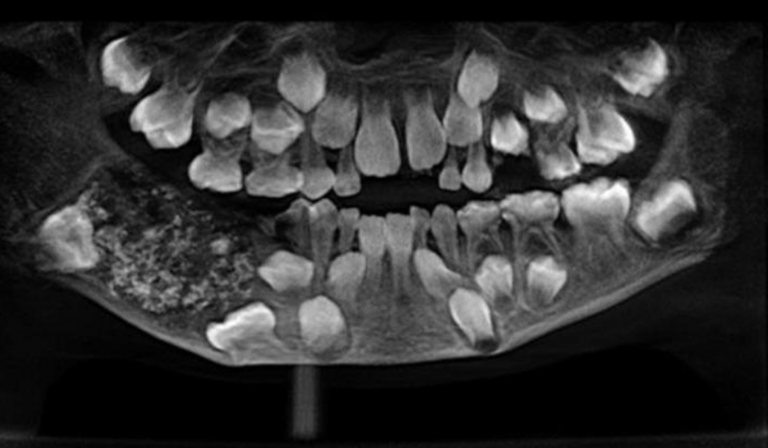

Dentistas de la India confirmaron que encontraron 526 piezas dentales extra en la boca de un pequeño que acudió a la consulta con dolor de mandíbula.

El centro médico Saveetha Dental College and Hospital en Chennai, India, dijo que el niño de tres años de edad ingresó con una hinchazón en la boca, pero nunca esperaron encontrar esa desmesurada cifra de dientes.

El hecho ha supuesto el primer caso médico de semejantes características documentado en la historia del hospital.